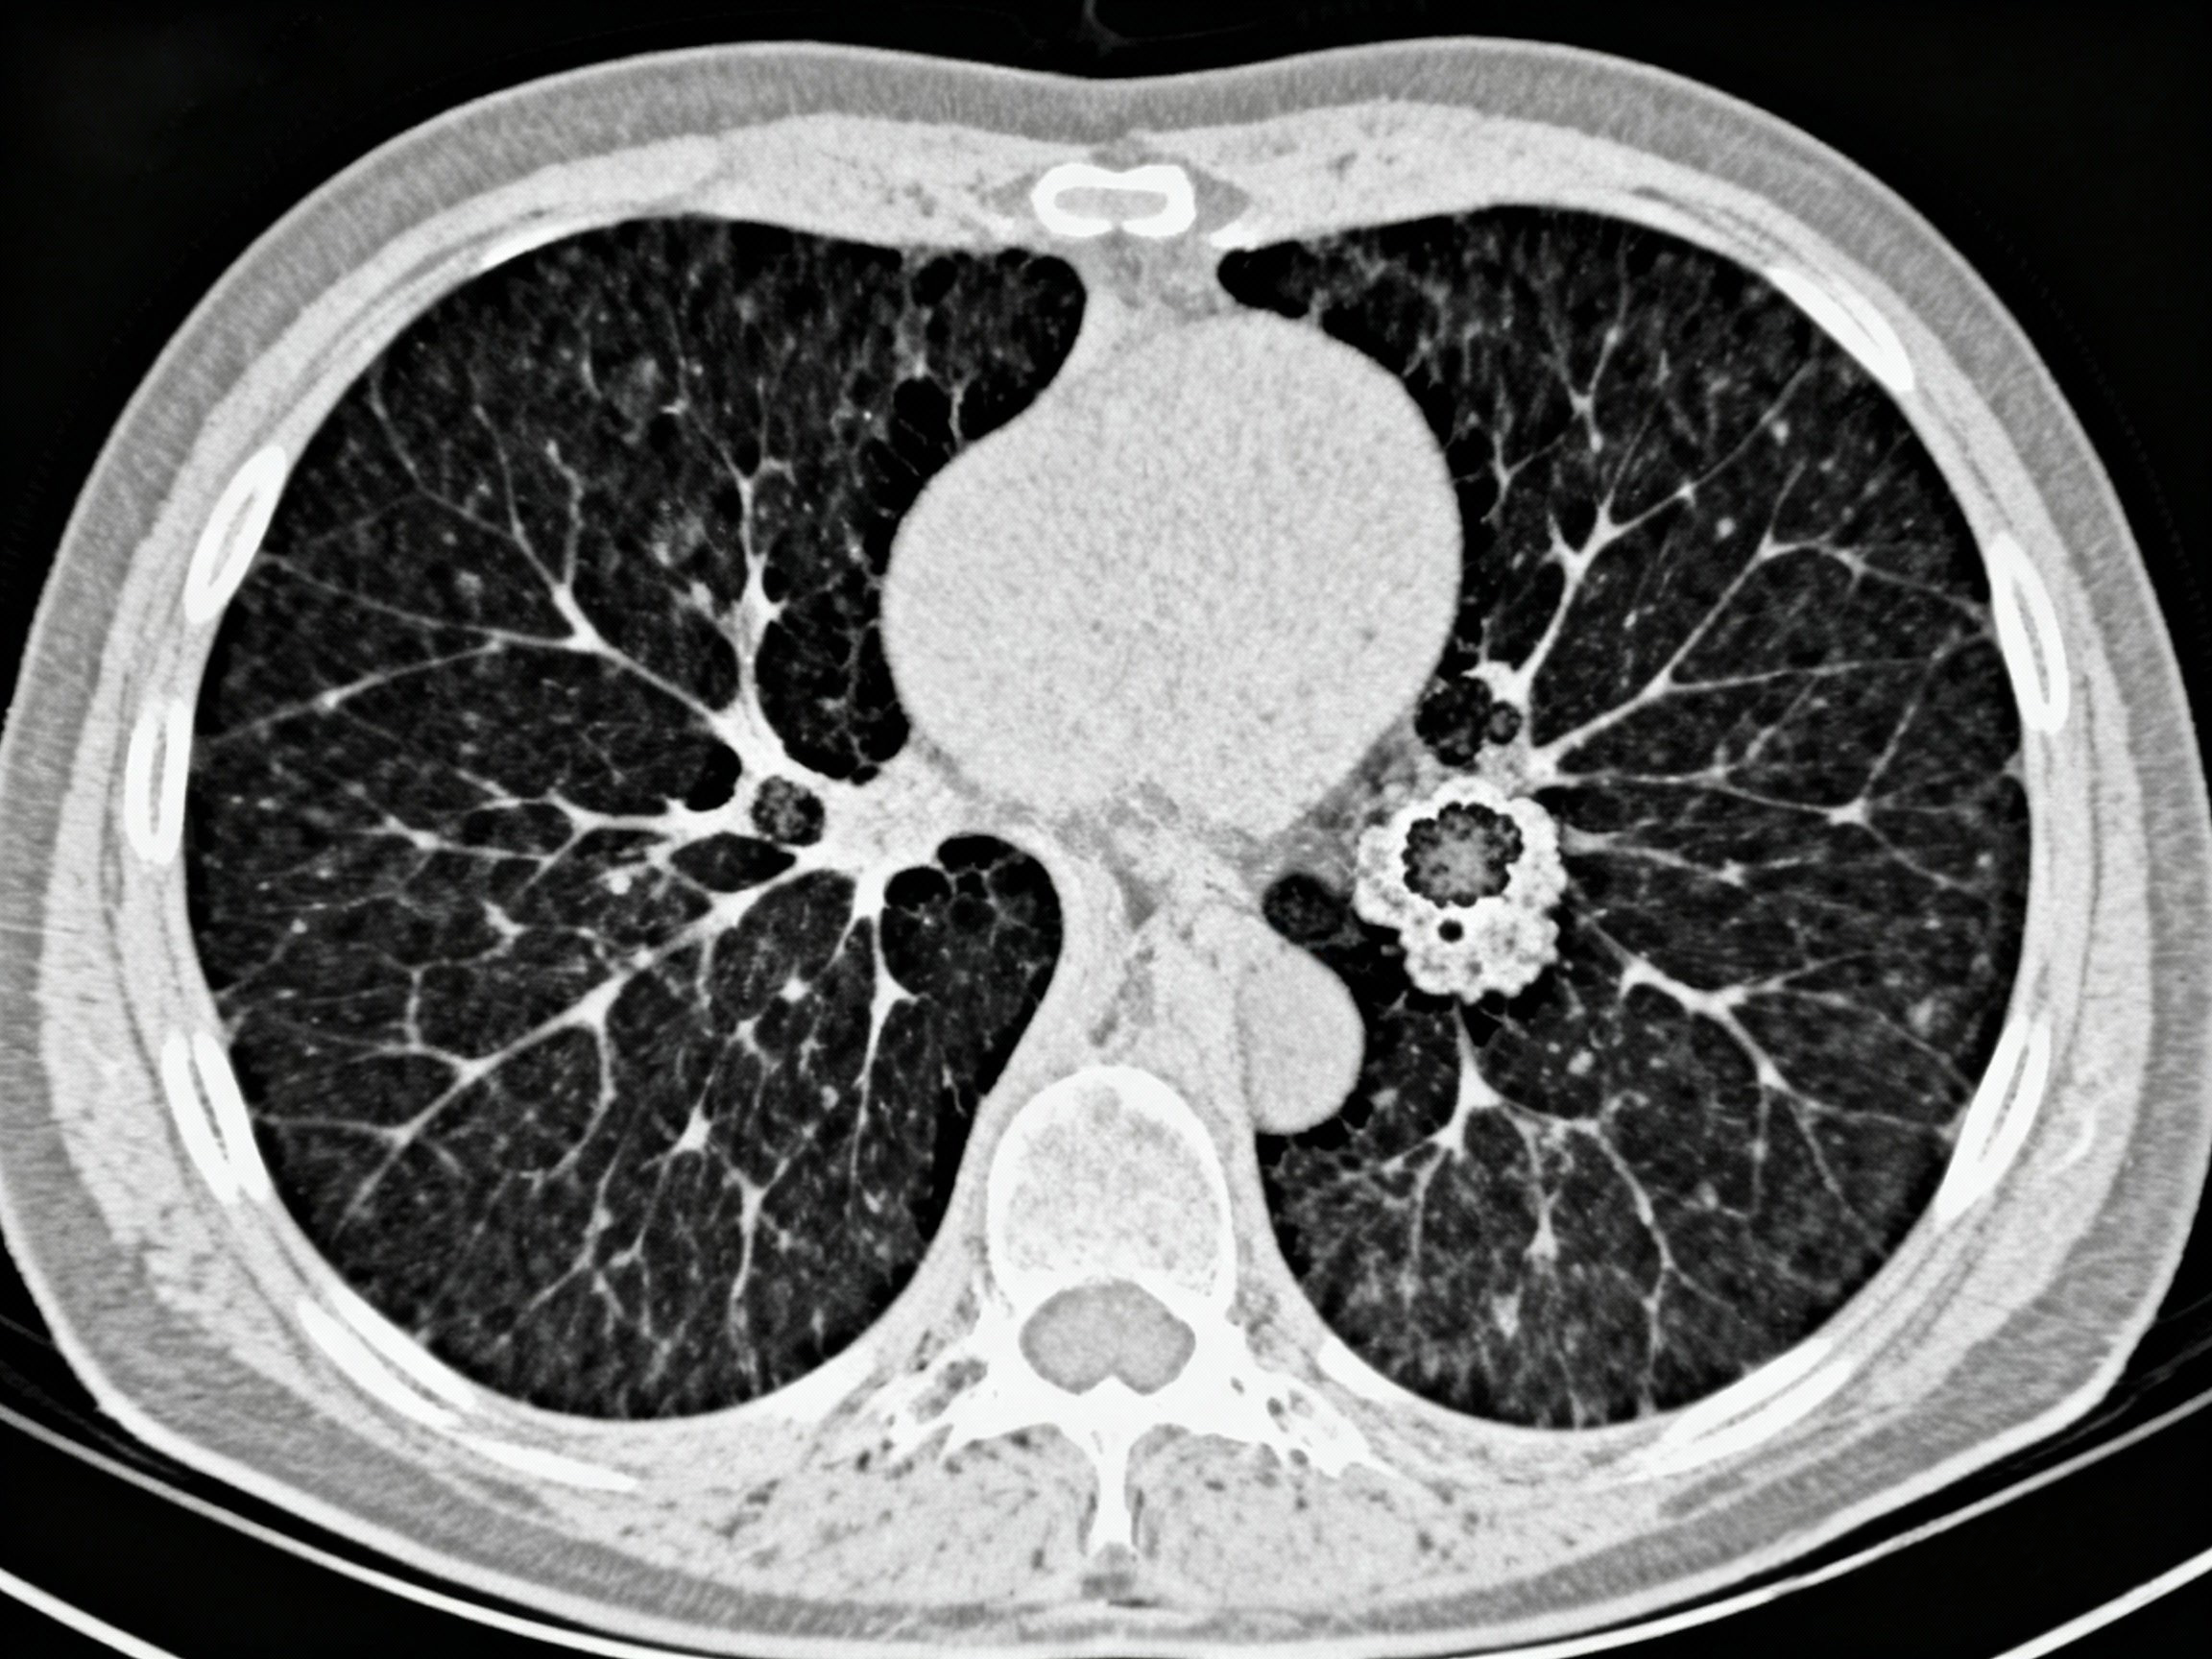

边主任调取了张先生的CT影像图,根据他右肺上的结节情况,开了两周的抗生素嘱其服用,同时要求他注意调整生活节奏,不要熬夜,服药后1.5个月再复查,同时开具了“高分辨CT”预约检查单。

此次复查结果与2024年体检以及2025年9月体检比较,显示“肺结节”依然存在,大小有变化,且发现“多发结节”。

张先生非常焦虑,他犹豫不决地找到六院胸外科专家主任医师杨异问:“要不就开刀吧?”杨主任看了张先生的片子,耐心地为张先生解释道:“片子拍摄的条件不一样,前两次是平扫CT,最近的一次是高分辨率CT,看得很清楚。肺结节的大小变化有可能条件不一样会导致这种变化。所以右面大的结节有可能是个良性的‘错构瘤’,左边有一个是后来新出现的,似乎这个比以前也明显了,关键是两种CT,不是一个条件的话,比较就很困难。现在肺结节患者很多,关键是要随访,看看是否有变化。过个半年,再复查高分辨率胸部CT看一看。如果有变化的,肯定要考虑手术。没变化可以再随访。”